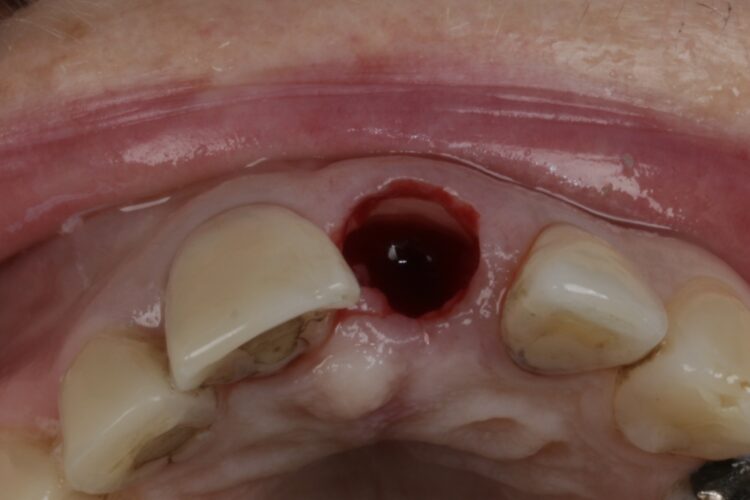

3. Root fracture:

Sub-crestal oblique or vertical root fractures can cause a lot of bone damage rapidly and I consider these to be urgent if I want to maintain bone. There is nothing to be gained by keeping these, they should be removed immediately or referred to the implantologist with a degree of urgency. Regrettably even then it’s often too late.